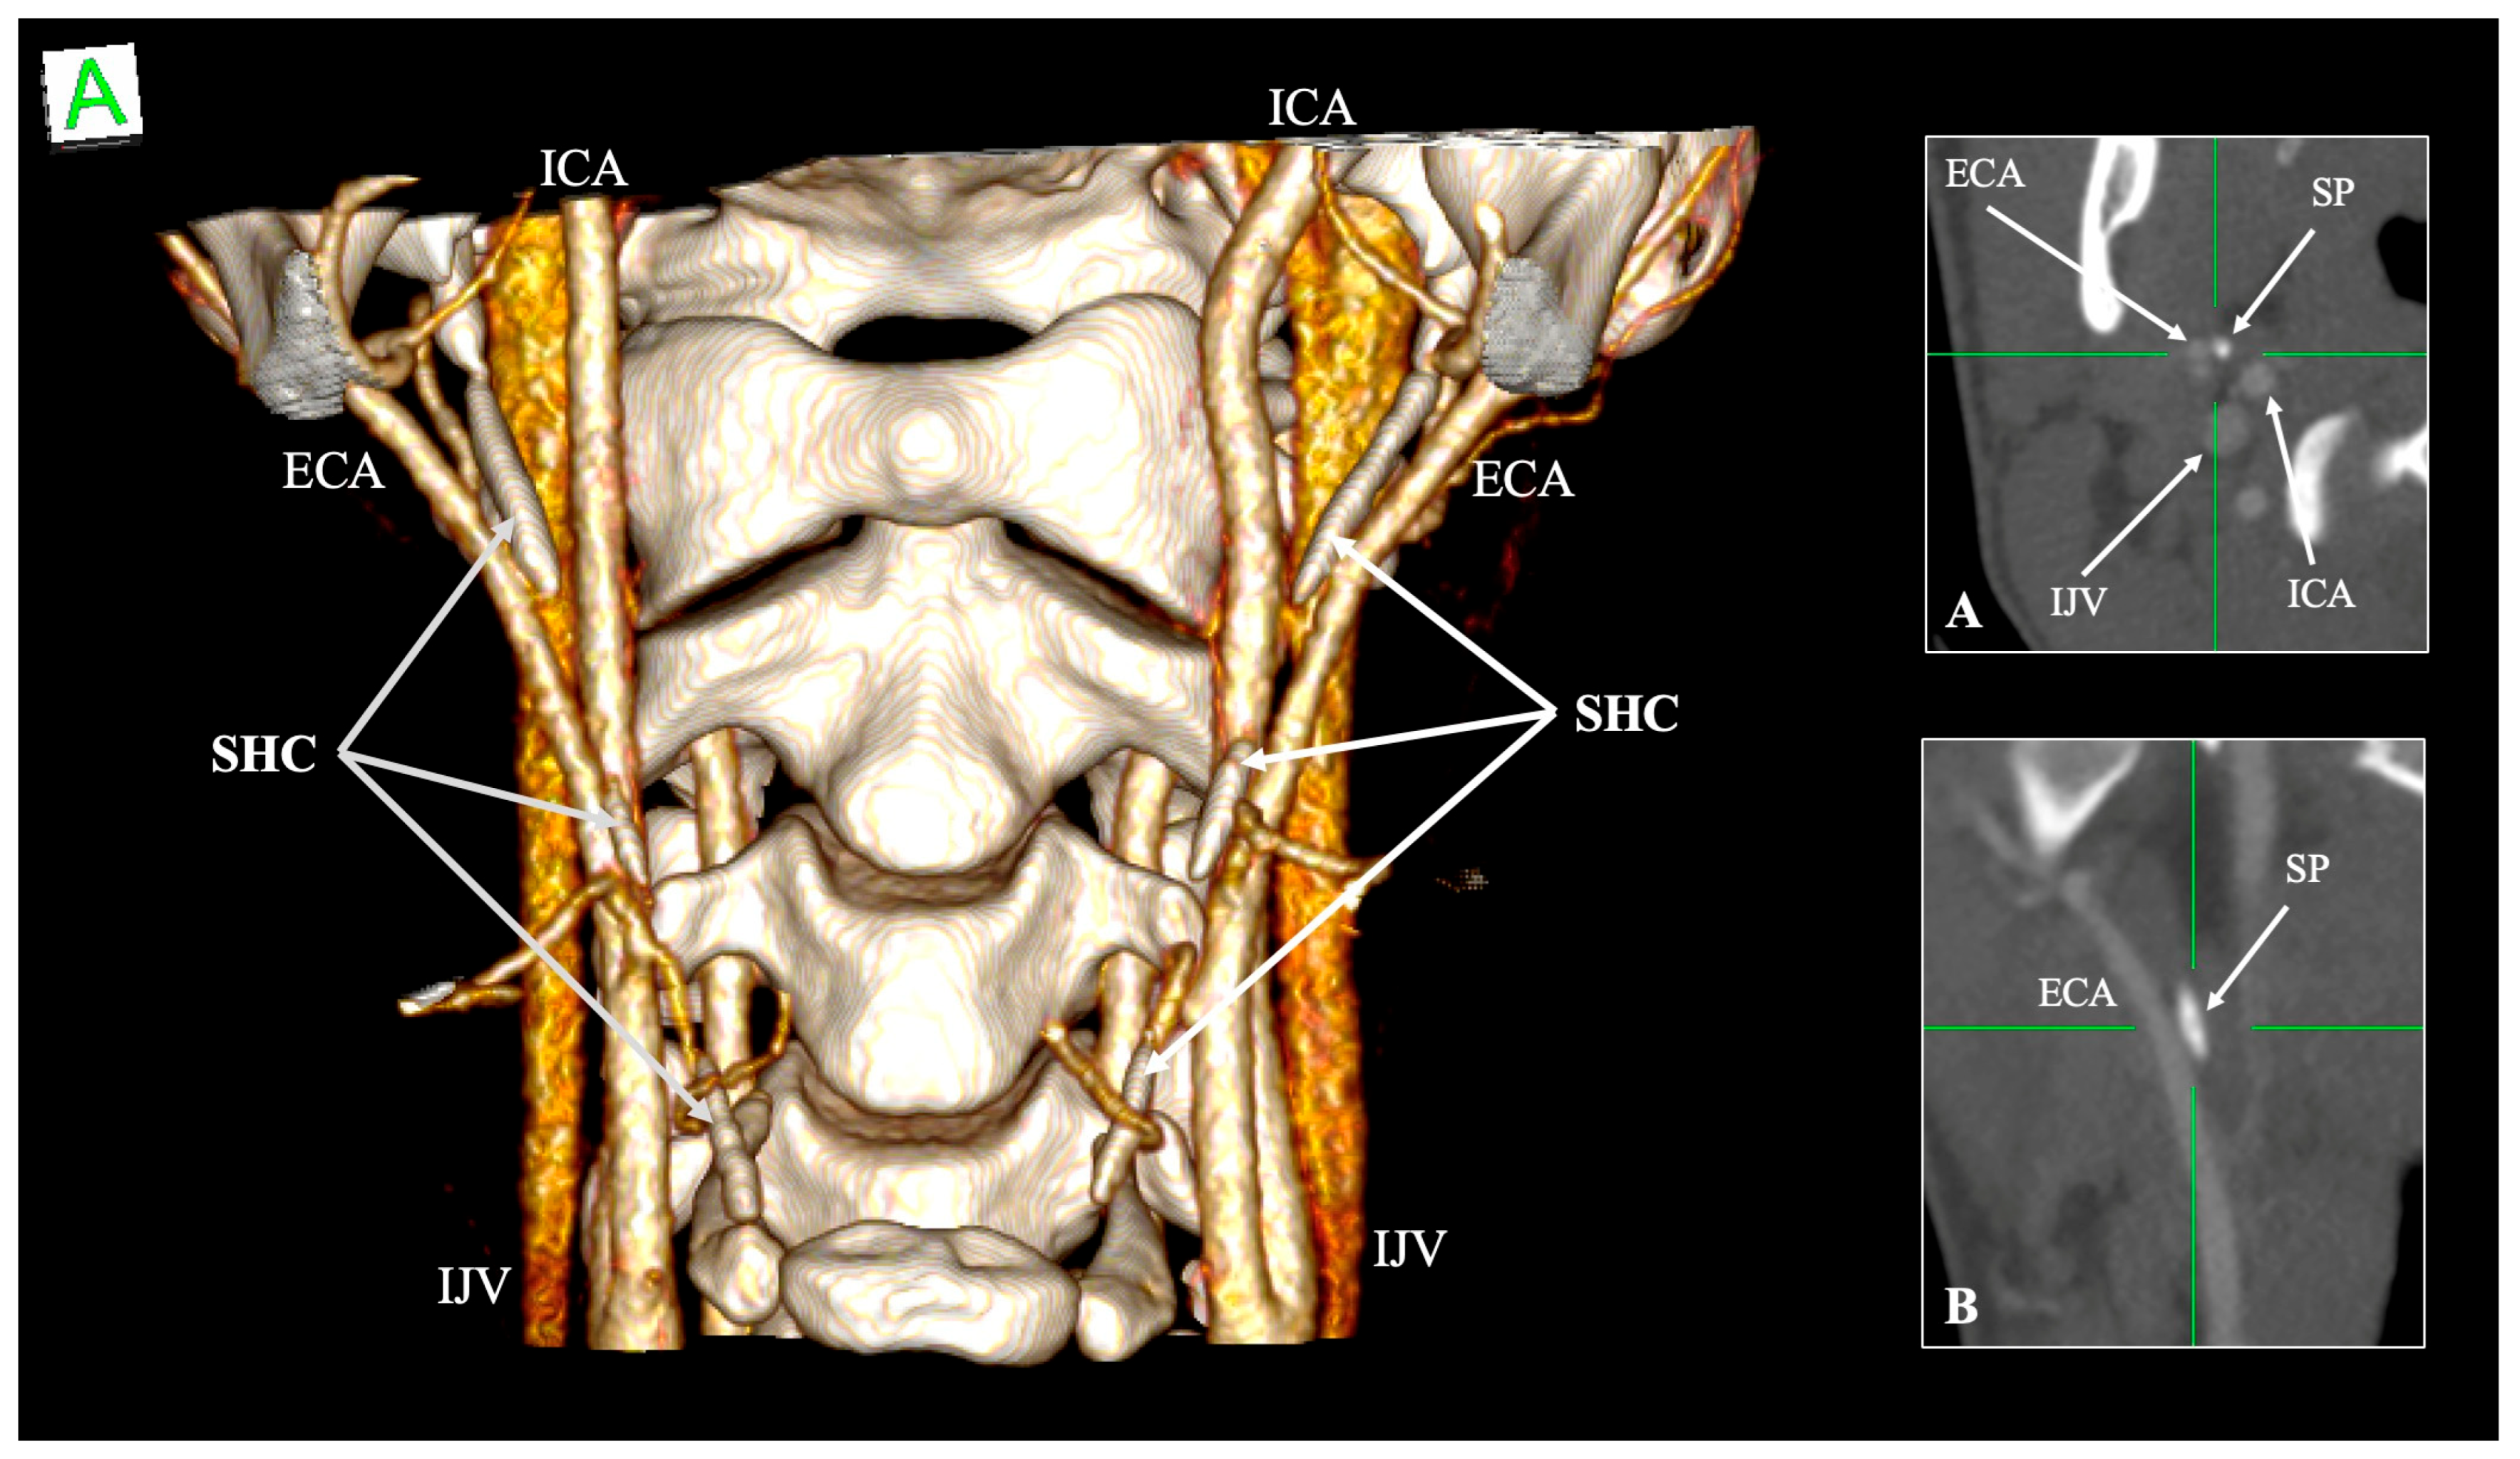

4.5. Relationship with Neurovascular Structures

- Jugular variant (Eagle jugular syndrome): Zamboni et al. [55] described compression of the IJV between the SP and the C1 transverse process, producing intracranial hypertension, papilledema, venous congestion, and even peri-mesencephalic hemorrhage [55]. Headache and orbital symptoms dominate, distinguishing it from the carotid subtype [56].

| Internal jugular vein (IJV) | Posterolateral to SP within the carotid sheath | Compression between SP and C1 transverse process (“jugular nutcracker”) | Intracranial hypertension, venous congestion, hemorrhage | Triantafyllou et al. [48] |